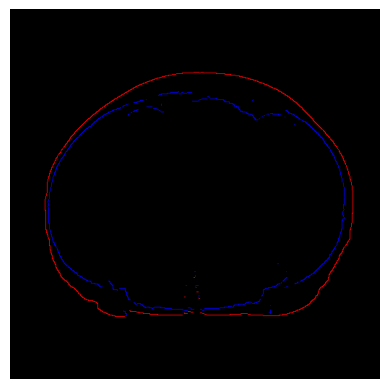

Refer to caption

(a) Original CT Scan (binarised based on Hounds Field Unit.

(b) Marking outer boundary (skin) based on contours (erroneous).

(c) Marking outer and inner boundaries using our algorithm.

(d) Segmenting the subcutaneous fat using our CV algorithm.

Figure 2: Comparison of our algorithm with the classical approach of contours, and segmentation of subcutaneous fat using our algorithm

Our algorithm was also able to demarcate the boundary of regions, which were not possible with commonly used CV algorithms. For example, figure 2 shows a comparison of results of convex-hull, contours and our CV based fat ratio algorithm in segmenting the subcutaneous fat from torso (visceral) fat on an images where fat is white (binarised based on HU values).